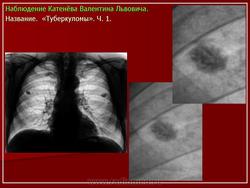

1. Множственные туберкулемы с распадом. В верхней доле правого легкого расположены множественные округлые тени, диаметром 1.5-2 см. средней интенсивности, с просветлением в центре, с четкими контурами.

2. Туберкулема в фазе распада. На томограммах в верхней долях правого и левого легкого определяются округлые тени, с четкими контурами, размерами 6 х 7 см. средней интенсивности, с просветлениями внутри.